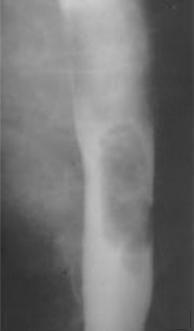

4 Polyp fibrovasculaire

: Tumeurs conjontives de oesophage . Lesion fibreuse

et de graisse sous muqueuse au

ni veau de oesophage peut pedicule dans lumiere oesophagien

. Devenir volumineux et differentiel avec carcinome a

cellule fusiformes . Diagnoctic par TOGD , IRM T2 et CT

scanner pour recherche la presence de graisse du tumeur .

Diagnostic ( + ) par anapath .